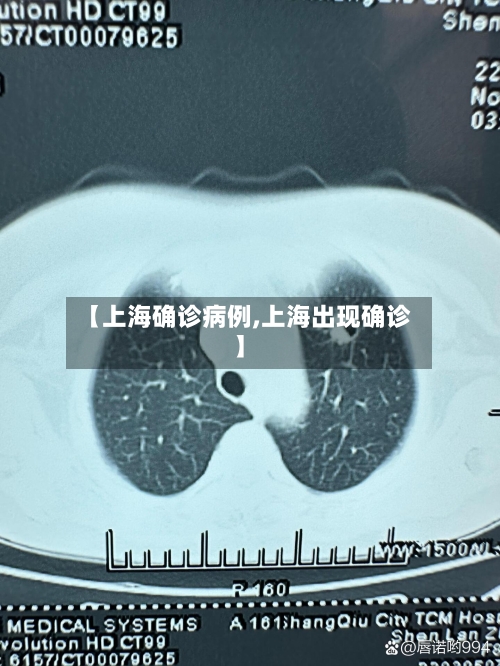

【上海确诊病例,上海出现确诊】

上海9日新增1例本地确诊病例,新增4例境外输入病例